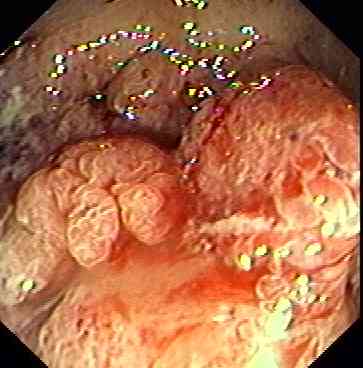

Appearance of rectal cancer.